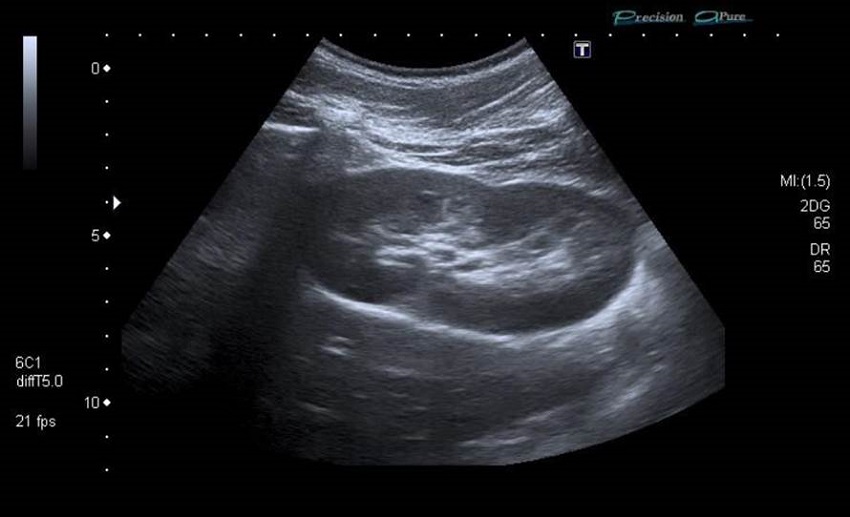

Se realiza la ecografía abdominal, donde se objetiva un riñón único derecho, no claramente compensador (figura 1). No se identifica el riñón izquierdo, pero se visualizan dos imágenes quísticas retrovesicales izquierdas, alargadas, que parecen desembocar en la próstata o el cuello vesical (figura 2). La más posterior, de 0,4 x 2,3 cm, probablemente corresponda a una dilatación de la vesícula seminal o del quiste mesonéfrico; el anterior, de 0,6 x 4,2 cm, podría corresponder a una dilatación del divertículo del remanente ureteral ciego con desembocadura baja (figura 3).